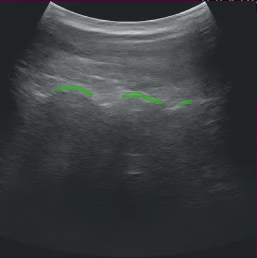

After modifying the application as instructed above, running the application should bring up the ultrasound video with a segmentation mask overlay similar to the image below.

app_ultrasound.png

Fig. 11 Ultrasound Segmentation